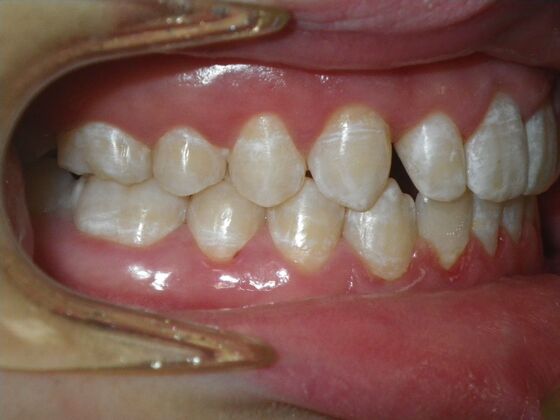

This patient does not like his anterior deep bite and the flaring of the right lateral incisor as well as anterior spacing. The solution was to correct his Class II molar relationship, Division II and deep anterior bite and close spacing as much as possible with addition of composite restorations on distals of lateral incisors. We began with utility archwires, eventually correcting Class II molar with distalizing appliance, and continued with final tip and torque. All that is left now is to ad composite to distals of upper lateral incisors.